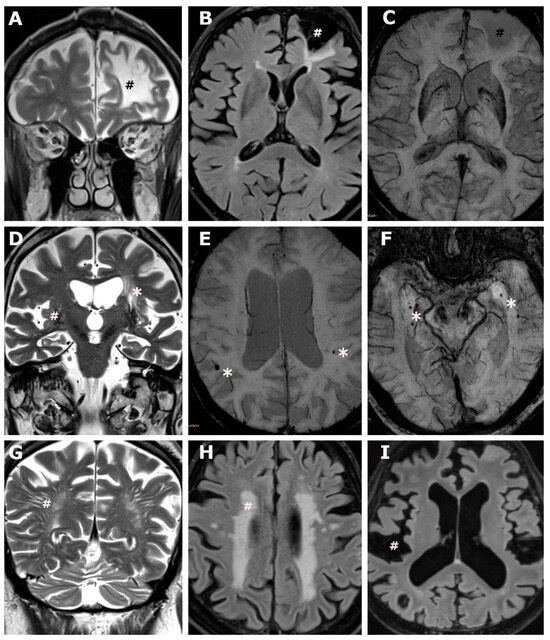

3.2. Cerebrovascular MRI Findings

3.3. Territorial Ischemia

| Territorial ischemic lesions, n (%) | 4 (5.3%) | 4 (12.5%) | 0 (0.0%) | 0.018 1 |

| Lacunar lesions, n (%) | 8 (10.7%) | 6 (18.8%) | 2 (4.7%) | 0.054 1 |

| Microbleeds, mean (SD) | 0.7 (1.2) | 1.4 (1.4) | 0.3 (0.7) | ≤0.001 1 |

| Centrally located microbleeds, mean (SD) | 0.1 (0.3) | 0.1 (0.3) | 0.0 (0.2) | 0.379 1 |

| Peripherally located microbleeds, mean (SD) | 0.7 (1.2) | 1.3 (1.4) | 0.2 (0.6) | ≤0.001 1 |

| Virchow–Robin spaces, mean (SD) | 30.3 (17.8) | 43.8 (18.4) | 20.6 (9.0) | ≤0.001 1 |

| Virchow–Robin spaces white matter, mean (SD) | 15.2 (8.7) | 22.6 (7.2) | 9.9 (5.1) | ≤0.001 1 |

| Virchow–Robin spaces deep grey matter, mean (SD) | 10.5 (10.3) | 15.8 (13.7) | 6.7 (4.0) | 0.001 1 |